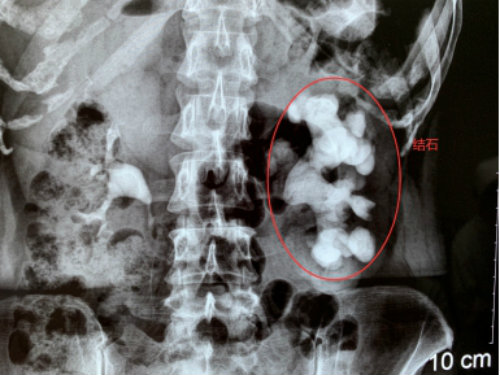

2019年11月18日,孝感一女子左腎里的結(jié)石長成“精”,長達(dá)12公分,形似一個(gè)“老生姜”,慕名到武漢京都結(jié)石醫(yī)院保腎取石,康復(fù)之際,被武漢多家媒體爭相報(bào)道后,一時(shí)間成了病房里的網(wǎng)紅。

18年前,魯女士在孝感當(dāng)?shù)蒯t(yī)院查出左腎小結(jié)石。因?yàn)閺膩頉]癥狀,她就沒管過。最近兩年,她又因長期右腰疼痛被查出腰椎間盤突出。上周,在準(zhǔn)備接受腰椎病治療的時(shí)候,CT結(jié)果提示她的左腎被結(jié)石撐滿,醫(yī)生建議她趕緊手術(shù),否則腎可能不保。

內(nèi)心十分害怕的魯女士專程趕到親戚推薦的武漢京都結(jié)石醫(yī)院,醫(yī)生指出,說所患的是臨床上比較罕見的巨大鹿角形結(jié)石,處理起來很棘手。幸運(yùn)的是,她的雙鏡聯(lián)合微創(chuàng)保腎取石手術(shù)很成功,左腎里的“姜王”結(jié)石在一期手術(shù)中得到了有效處理,術(shù)后也恢復(fù)得不錯(cuò)。